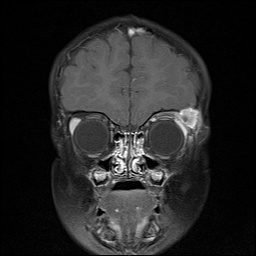

An MRI was obtained when the patient arrived at UIHC as part of his inpatient workup and corroborated the CT findings (Figure 3 and 4).

Figures 3 and 4: These T1 (left) and T2 (right) post-contrast coronal MRI images demonstrate an enhancing mass in the superotemporal aspect of the left orbit. Note that the homogenous soft tissue characteristics of the lesion are well-defined with this imaging modality.

Figure 3. T1 post-contrast coronal MRI image demonstrate an enhancing mass in the superotemporal aspect of the left orbit. Note that the homogenous soft tissue characteristics of the lesion are well-defined with this imaging modality. Figure 4. T2 post-contrast coronal MRI image demonstrates an enhancing mass in the superotemporal aspect of the left orbit.